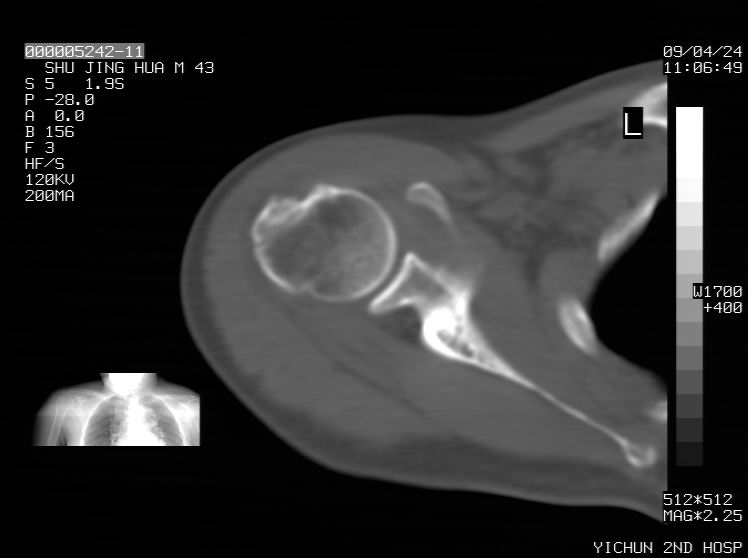

标题: CT19569:请会诊,女50岁,右肩疼痛数月 [打印本页]

标题: CT19569:请会诊,女50岁,右肩疼痛数月

钙化性肌腱炎

是指钙盐沉积在变性肌腱中的一种无菌性炎症,常见于肩关节的肩袖肌腱,引起肩部疼痛和活动受限。分为急性和慢性两种类型,急性型有肩关节突然出现急性疼痛的发作史,夜间可痛醒。